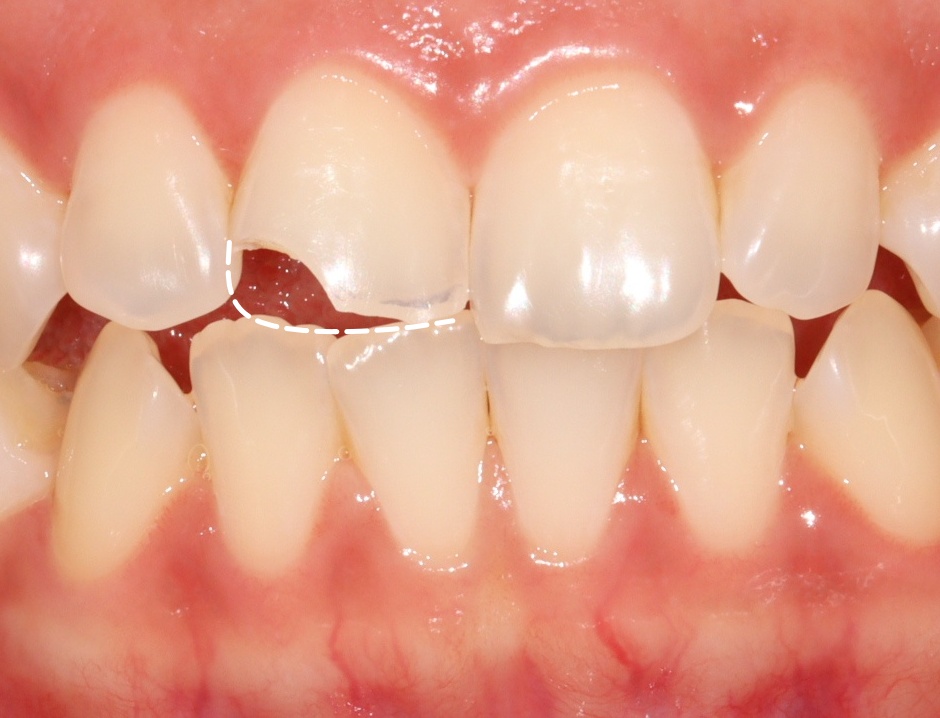

구강 내 모습을 확인해 보면

상악 중절치의 절단 부위가

약 1/3 정도 파절된 것을

관찰할 수 있는데요.

다행히 치수가 노출되지 않은

법랑질-상아질 파절로 확인됩니다.